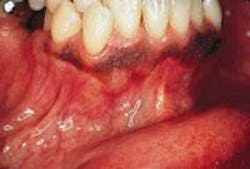

CASE 6

Peripheral giant cell granuloma (PGCG)

1. What causes a PGCG?

a. irritation

b. injury

c. both a & b

d. none of the above

2. Where is the PGCG likely to occur?

a. hard palate

b. gingiva

c. floor of mouth

d. any of the above

3. What is the preferred treatment for the PGCG?

a. surgical excision

b. removal of irritation sources (calculus)

c. no treatment necessary

d. both a & b